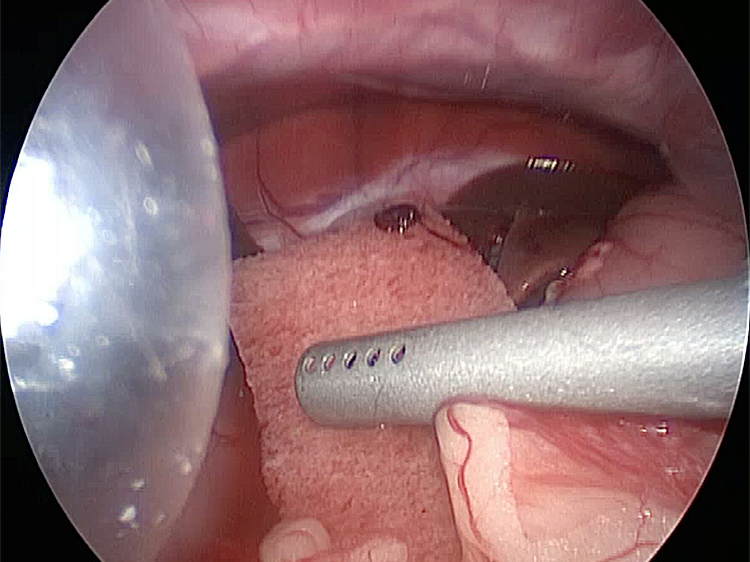

お腹にトロッカーを4本挿入し、そこから鉗子とカメラを入れて胆嚢を肝臓から剥がしていきます。 カメラで拡大しながら見ることができるので開腹手術よりも視野が確保できます。

手術の様子

胆嚢の周囲の脂肪や膵臓、十二指腸が激しく癒着し剥離が困難な状態でした。胆嚢は全く確認することができませんでした。

少しずつ癒着を剥がして胆嚢が確認できるようになってきました。 こんなに癒着していることはあまりないので過去に膵炎や胆嚢炎を起こし苦しい時期があったことが推測されました。 それにしてもなかなか胆嚢はでてきませんでした。